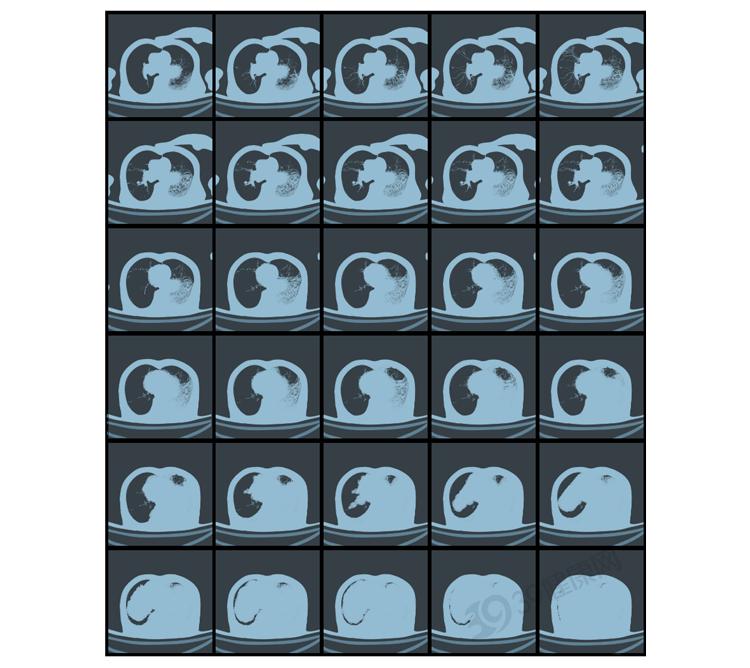

CT(计算机断层扫描)是一种高精度医学影像检查,能够通过X射线获取身体内部的详细图像,帮助医生快速、准确地判断疾病。

其主要有两种类型:平扫CT、增强CT。区别在于是否使用造影剂、成像效果以及适用场景。

平扫CT是最基础的类型,属于无创检查,不使用造影剂,直接进行X射线扫描,适用于基础检查,如脑出血、肺炎、骨折等。

增强CT则需要在检查前通过静脉注射造影剂,让血管、器官、病变部位更为清晰,多用于判断肿瘤良恶性、血管病变、脏器功能异常等。

肺癌、肺气肿、肺炎、纵膈疾病等胸部问题;

如果说X光是一张照片,那CT就是把身体“切”成一层层薄片,能看到更多细节。

辐射量比X光高,但比想象中安全,适用于癌症筛查、肺部精细检查、脑出血等。